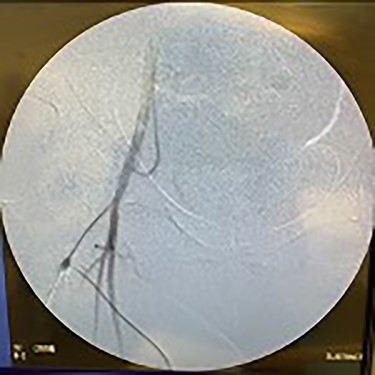

Catheter arteriogram results showed significant occlusion of the left iliac artery (Figs 3 and 4), the right iliac artery (Fig. 1), as well as the distal abdominal aorta (Fig. 2). There were numerous collateral vessels noted, indicating the presence of long-standing proximal stenosis (Fig. 1). The decision was made to use angioplasty to help widen the areas of stenosis. An 8 mm × 40 mm Passeo balloon was advanced from the right femoral artery into the left iliac artery (Fig. 7) and insufflated to 6 mmHg (Fig. 6). The balloon was allowed to remain expanded for 1 min and then was deflated. Next, the distal aorta was repaired in a similar fashion. The balloon was advanced into the distal aorta from the right femoral access and insufflated to 12 mmHg (Fig. 8). The balloon was allowed to remain expanded for 90 s.

Fluoroscopy of right iliac artery showing vast collateral vascular formation, indicating long-standing proximal obstruction.